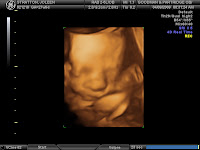

1)Jojo: Joleen had some stomach tightness that we thought was nothing but it turns out it may have been contractions. So, doc has put her on light duty (which means she gets more vacation because she can't stand up all day at work!) and she has just been hanging out at home trying to take it easy. She has another appointment in the morning so we will see what they have to say then.